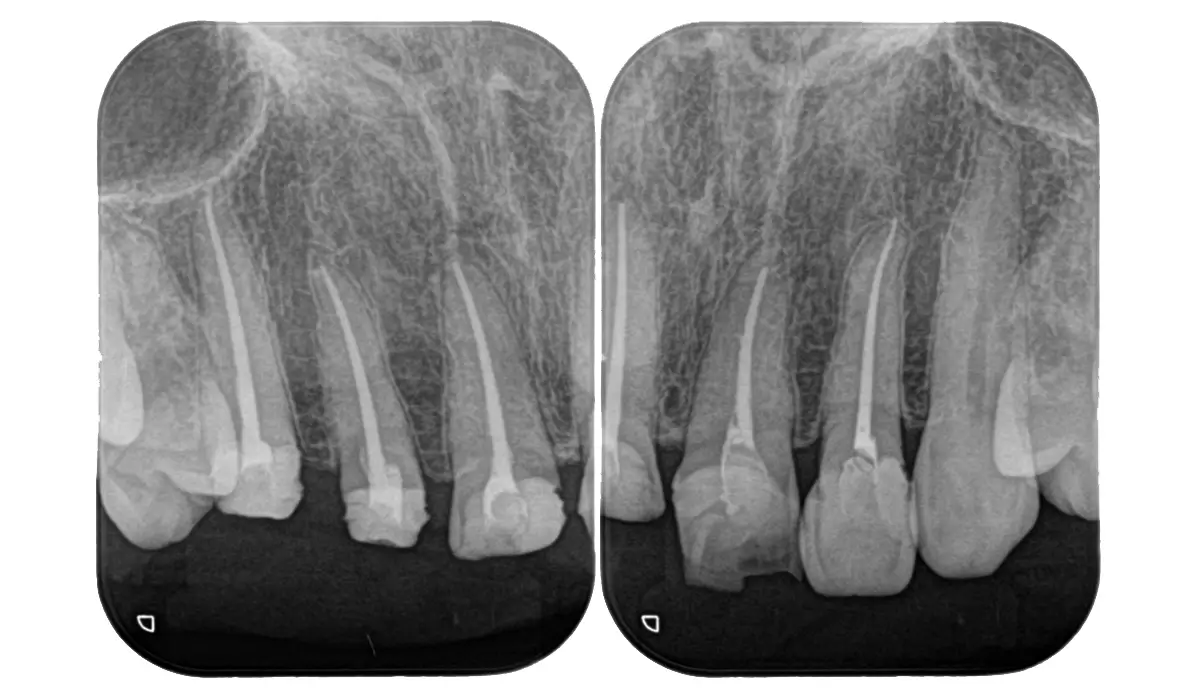

カリエス除去後に隔壁の作製を行い、ラバーダムシートによる環境整備を行って根管治療を行いました。

当院では根管治療においてイニシャルトリートメントこそ最重要と考えています。ここを間違えなければ5年生存率90%、10年生存率80%という世界的な統計報告を十分達成可能と考えています。